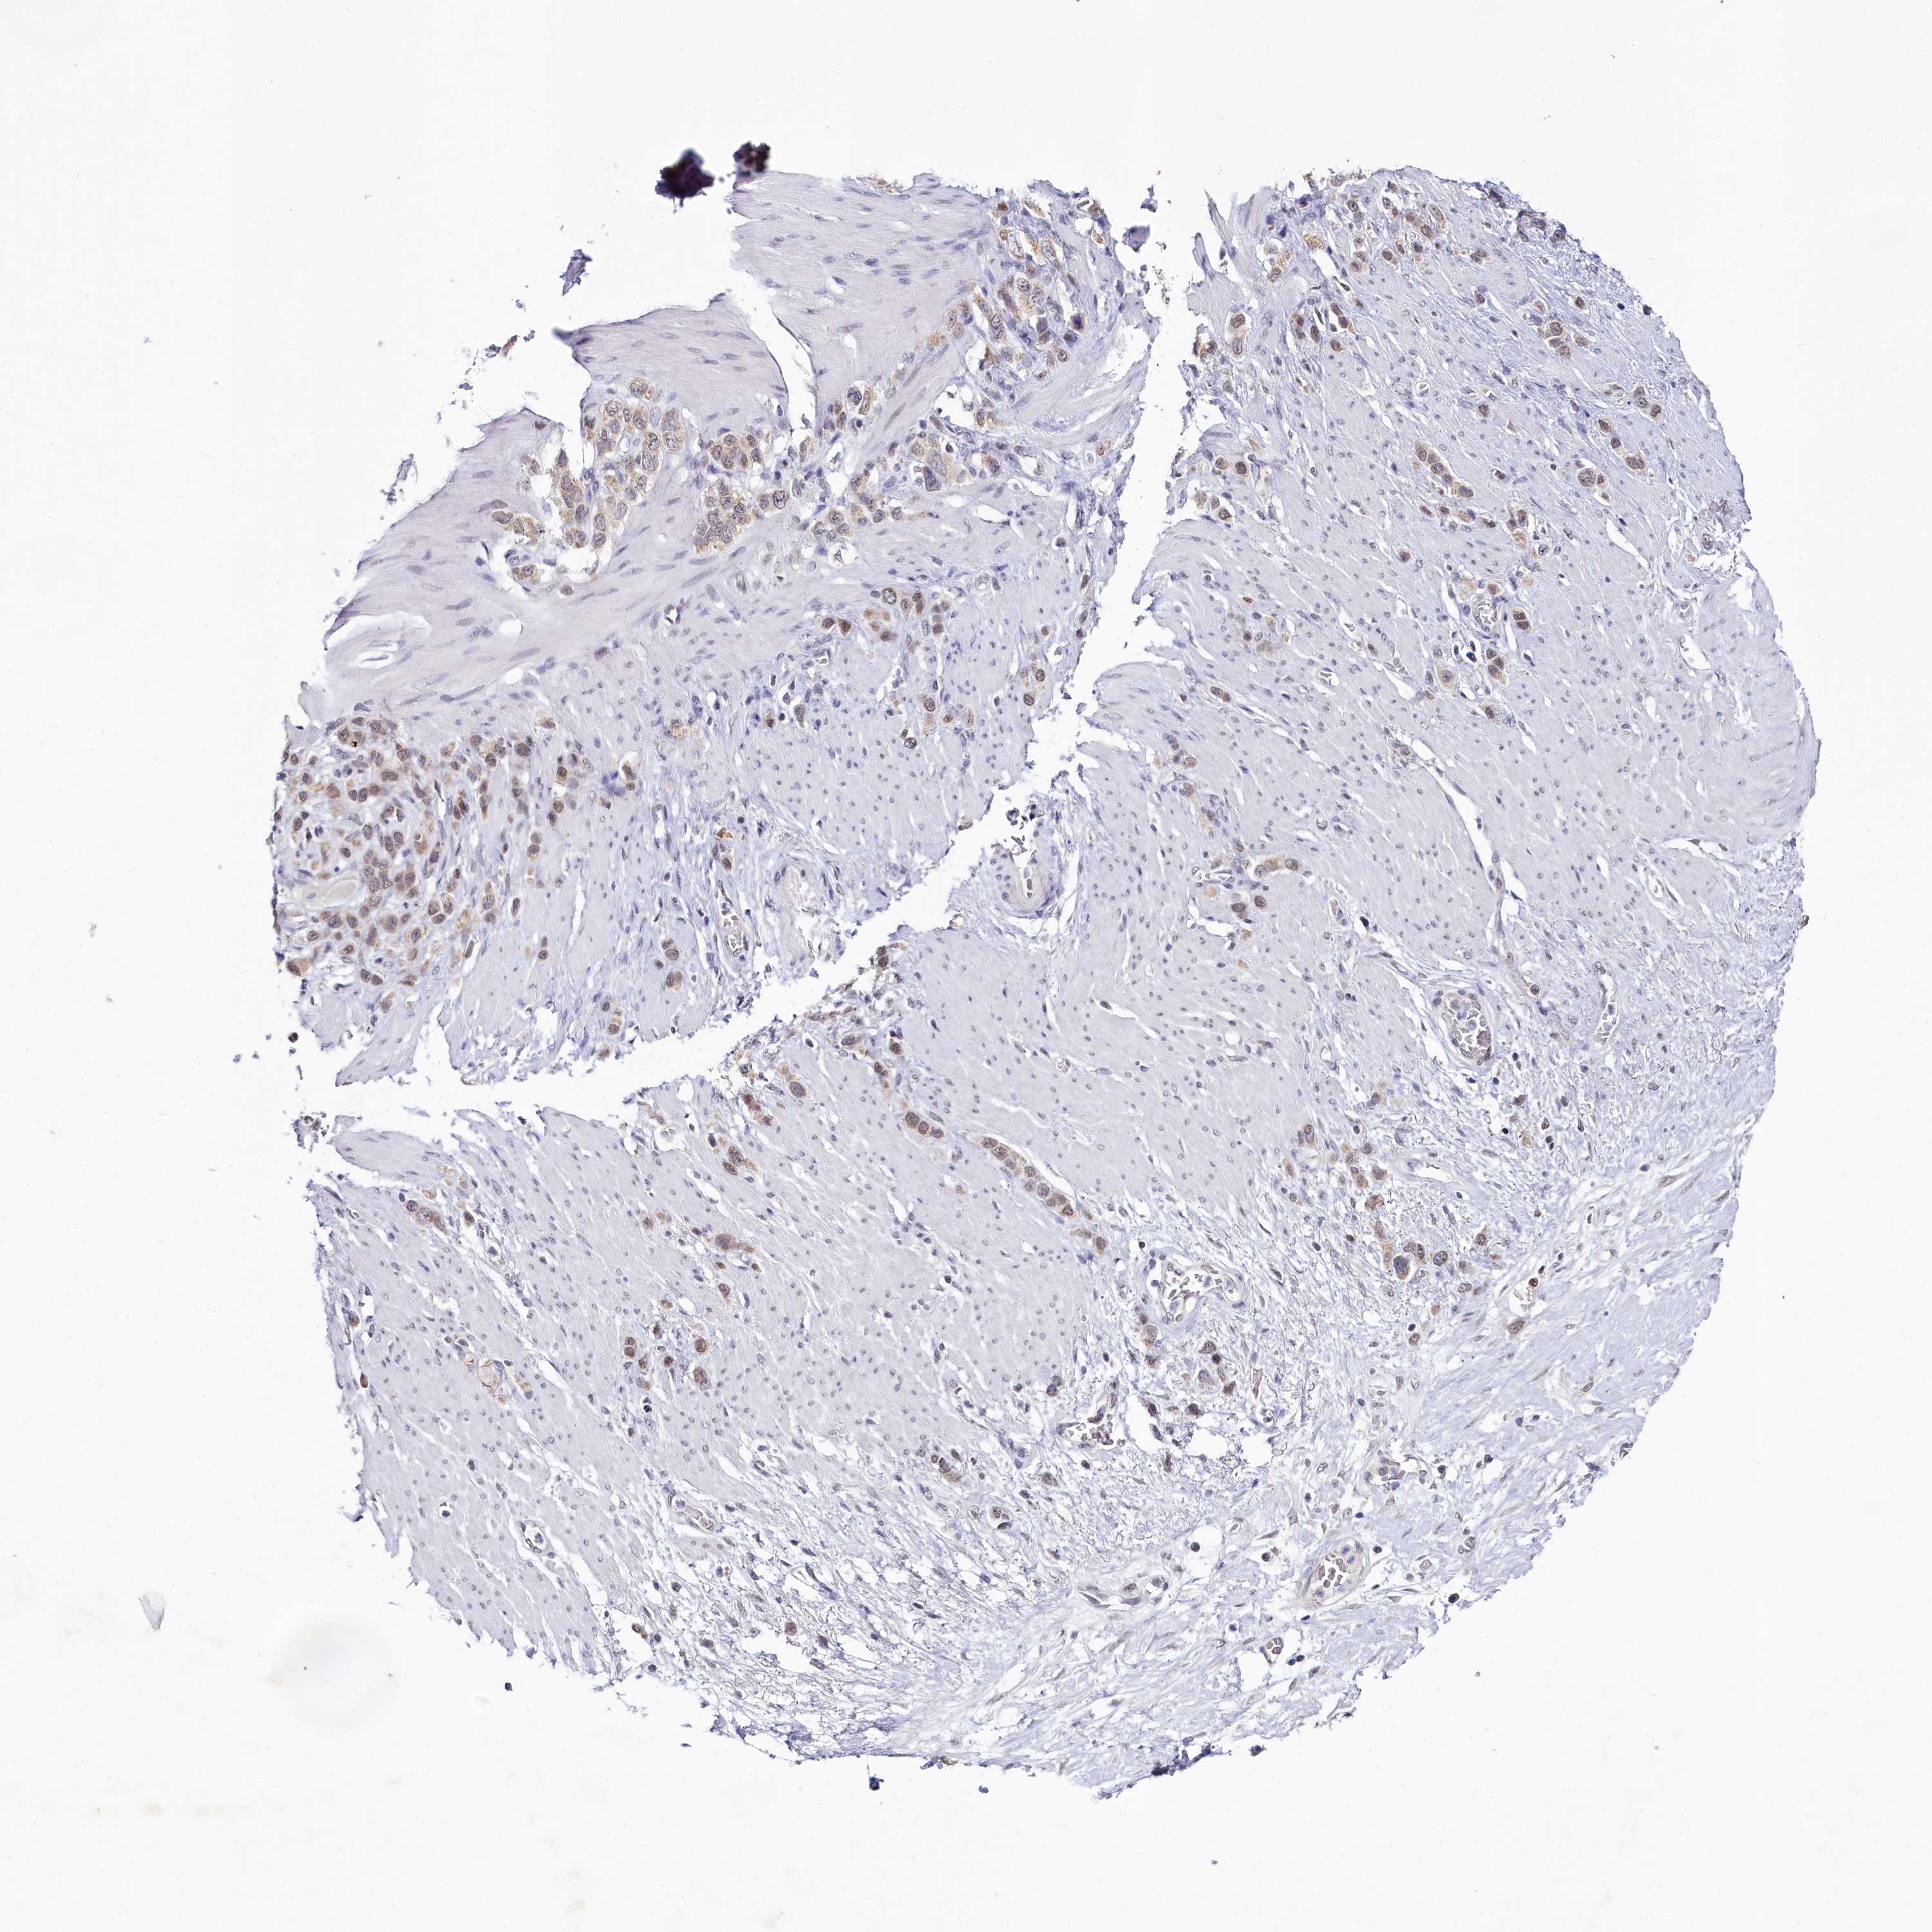

STOMACH CANCER - Protein expressioni

A mouse-over function shows sample information and annotation data. Click on an image to view it in a full screen mode. Samples can be filtered based on level of antibody staining by selecting one or several of the following categories: high, medium, low and not detected. The assay and annotation is described here.

Antibody stainingi

Antibody staining in the annotated cell types in the current human tissue is reported as not detected, low, medium, or high, based on conventional immunohistochemistry profiling in selected tissues. This score is based on the combination of the staining intensity and fraction of stained cells.

Each image is clickable and will lead to virtual microscopy that enables deeper exploration of all samples and also displays staining intensity scores, fraction scores and subcellular localization as well as patient and tissue information for each sample.

Antibody HPA038902

Antibody HPA038903

Staining

High

Medium

Low

Not detected

Intensity

Strong

Moderate

Weak

Negative

Quantity

>75%

75%-25%

<25%

None

Location

Nuclear

Cytoplasmic/membranous

Cytoplasmic/membranous,nuclear

Adenocarcinoma, NOS

Adenocarcinoma, High grade